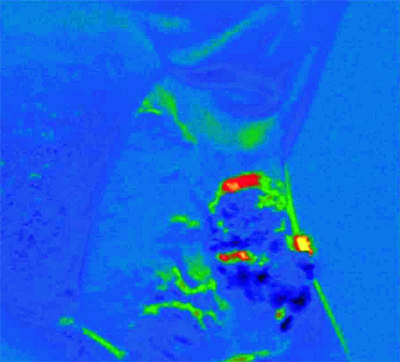

Andor’s SOLIS software then computes a ratio image of the area under investigation, based on the images captured at the two wavelengths, and generates a pseudo colour map (PCM), in which blue designates healthy tissue, red denotes dysplastic/pre-malignant tissue, and yellow identifies malignant tissue. This allows rapid visual differentiation of oral lesions and identification of regions with pre-malignant characteristics.